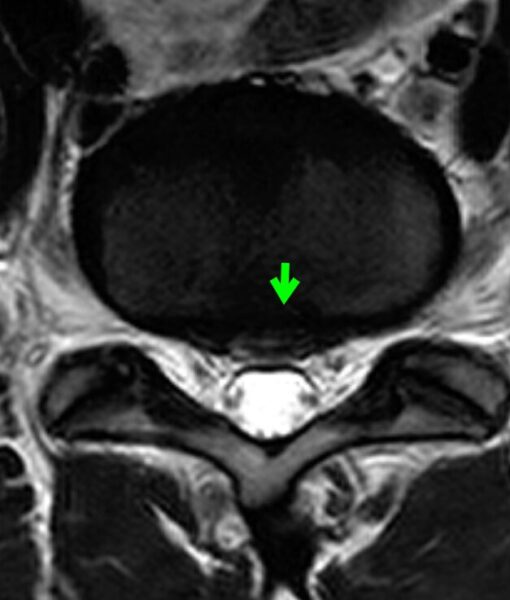

事故直後のMRI

事故直後のMRIでは、

腰椎椎間板ヘルニアを認めます。

〔画像①:事故直後MRI〕